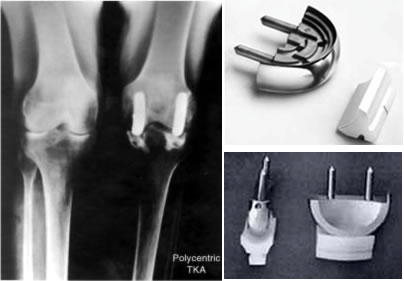

Illustration of Polycentric TKA design by F. Gunston 1969

Polycentric Radiographic Post-op view and product

John Charnley had no active role in Gunston’s knee work, however, Charnley did develop his own unicompartmental knee that was introduced and distributed by Thackeray as the Load Angle Inlay.[1]

This featured a convex UHMWPE femoral component articulating against a fl at metallic plateau.[1] Charnley’s design did not survive due to loosening, deformation and wear of the plastic femoral component. However, the tibial (metal) components stood up remarkably well.[2,3]